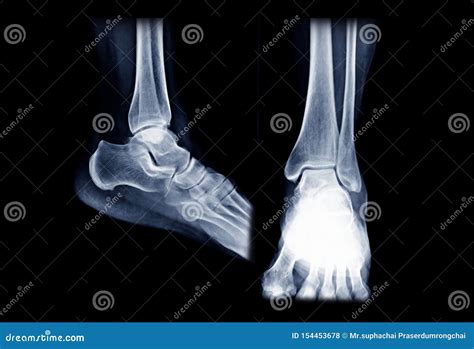

Experiencing persistent pain, swelling, or discomfort in your foot often leads to a diagnostic journey that frequently includes medical imaging. Among the most common diagnostic tools is the foot X-ray. When you receive your results, seeing the phrase Foot Xray Normal can be both a relief and a source of confusion. If you are experiencing pain, how can the imaging be "normal"? Understanding what this result means, why it happens, and what the next steps are is essential for navigating your path to recovery and pain management.

When a radiologist interprets your images and reports a Foot Xray Normal, it means that, based on the standard diagnostic criteria, there are no overt structural abnormalities detected. Specifically, the imaging technician and the radiologist are looking for clear indicators of injury or disease.

In a normal report, the following findings are typically absent:

• Fractures: No breaks, hairline cracks, or stress fractures in the bones of the foot (tarsals, metatarsals, or phalanges).

• Dislocations: The joints are properly aligned, and there is no evidence of bones being pushed out of place.

• Degenerative Changes: No significant signs of osteoarthritis, such as narrowing of joint spaces or bone spurs (osteophytes), beyond what is considered age-appropriate.

• Tumors or Infections: There are no visible suspicious masses, lesions, or signs of bone infection (osteomyelitis).

• Foreign Bodies: No objects, such as glass or metal, are identified within the soft tissue.

Essentially, the X-ray is confirming that the skeletal framework of your foot appears healthy and intact according to the images captured.